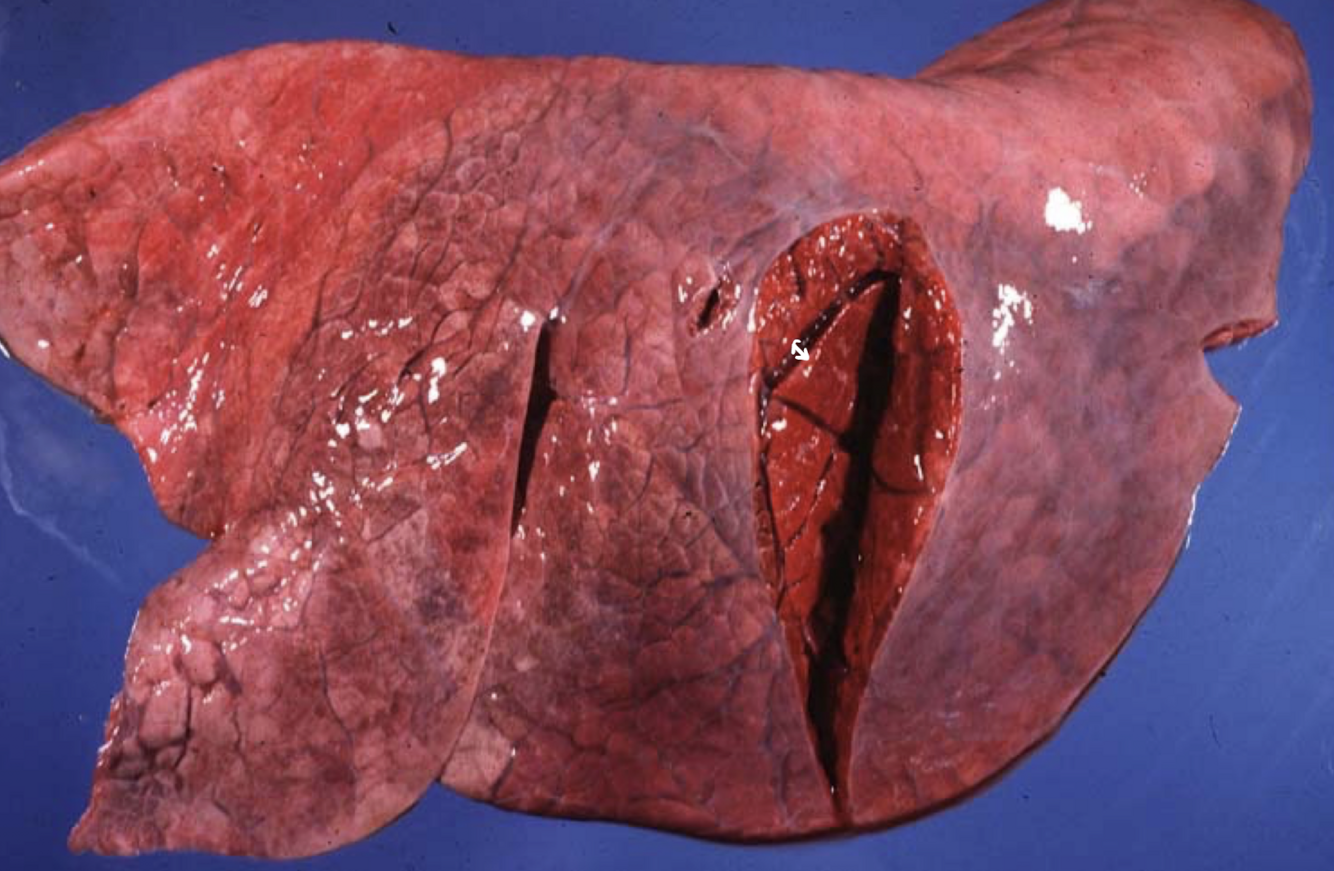

Nutmeg Liver

chronic, passive congestion of the liver due to RIGHT-sided heart failure